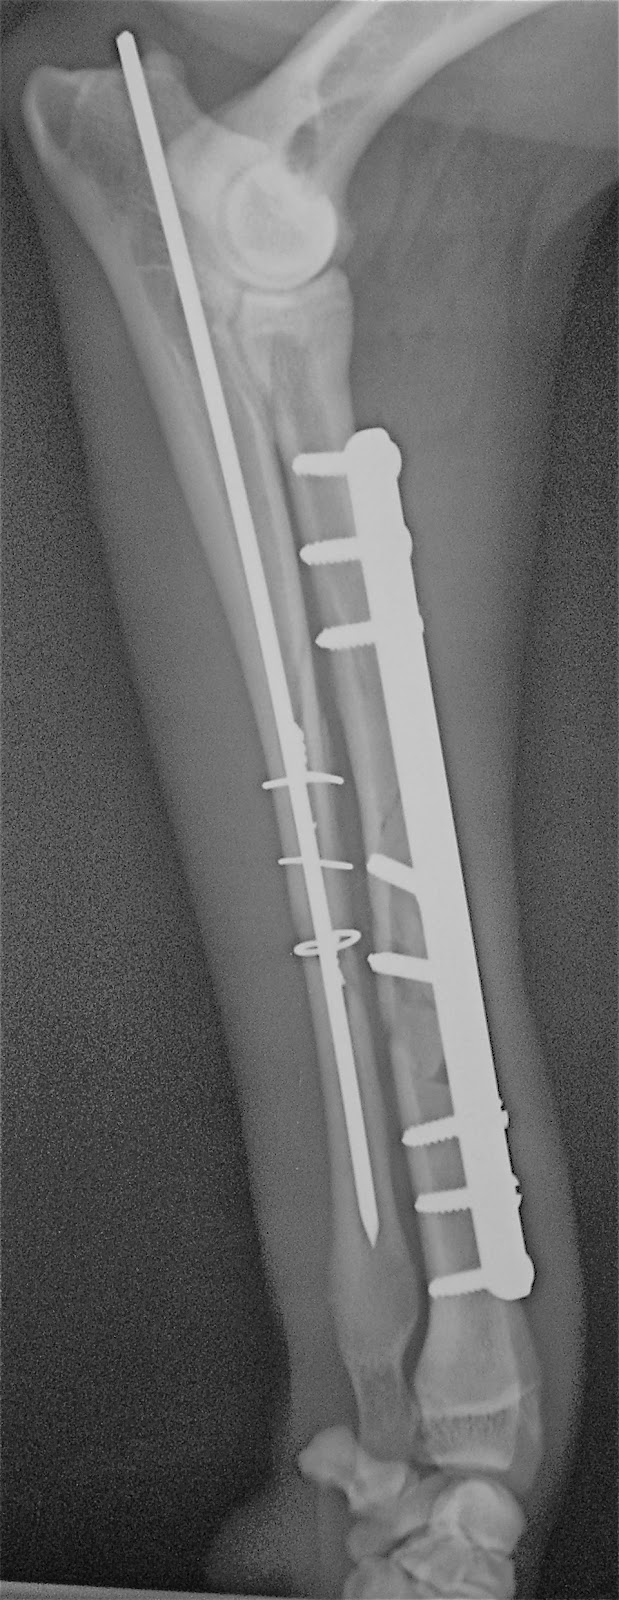

Συντριπτικό κάταγμα αντιβραχίου σε σκύλο από Πέτρος Μπεάκος08/01/201407/12/2017Σχολιάστε Προσθοπίσθια ακτινογραφία Πλάγια ακτινογραφία Οστεοσύνθεση κερκίδαςμε πλάκα και βίδες καιωλένης με ήλο και σύρμα Κοινοποιήστε: Στείλε ένα σύνδεσμο σε έναν φίλο(Ανοίγει σε νέο παράθυρο) Email Εκτύπωση(Ανοίγει σε νέο παράθυρο) Εκτύπωση Mοιραστείτε στο Facebook(Ανοίγει σε νέο παράθυρο) Facebook Μοιραστείτε στο X(Ανοίγει σε νέο παράθυρο) Χ Μου αρέσει! Φόρτωση... Σχετικά